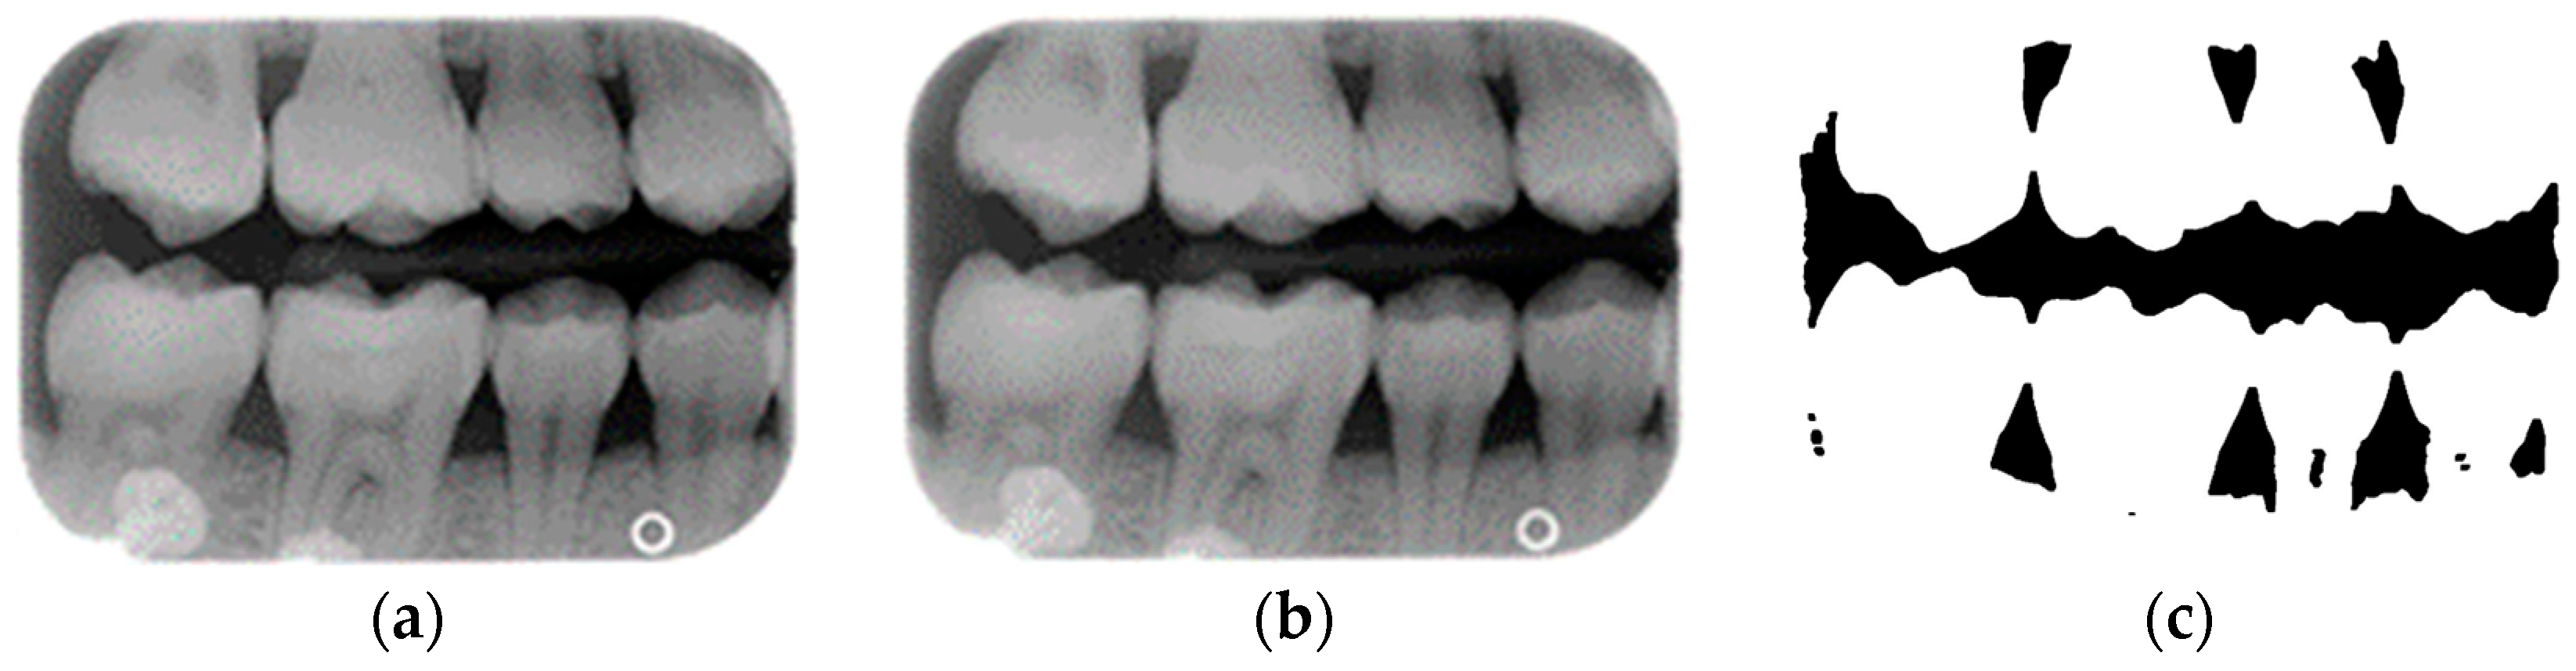

- Single-tooth extraction algorithm

A complete BW varies due to factors such as angle, exposure size, the number of teeth, and interproximal spacing. Using fixed parameters and thresholds can lead to misjudgments and low segmentation efficiency. To enhance flexibility and operability, the algorithm uses adaptive thresholds tailored to each BW based on brightness, size, and the number of teeth. Each BW is pre-processed before segmentation due to variations in mouth shape, tooth shape, and imaging angle. This study first applies to a gaussian high-pass filter to eliminate noise, reducing segmentation errors. Next, the images undergo binarization and erosion techniques to clarify background contours, making them easier to distinguish, as illustrated in Figure 3.

Due to angular issues in a BW, horizontal and vertical lines may not fully separate the teeth. This study addresses this by rotating and binarizing images multiple times to enhance the contrast between teeth and gaps. High-contrast images allow for accurate identification of tooth gaps through pixel horizontal projection as shown in Figure 4a. The image is divided horizontally into three parts, masking the upper and lower sections to focus on the middle, like the upper and lower sides of the red box in Figure 4b are masked. The valleys of the projection line in this region are identified as the x-minimum value, and the y-coordinate of the valley represents the vertical height separating the upper and lower rows of teeth after rotation. Additionally, during each rotation, a projection is made to identify the trough position in the middle of the image. The trough values (x-minimum) at each angle are compared to determining the optimal rotation angle for horizontal segmentation. Initially, the image is rotated within a range of plus or minus 15 degrees, in increments of 5 degrees. By comparing the trough values at each angle, the most suitable rotation angle for horizontal cutting is identified, as shown in Figure 4b.

According to Table 1. After performing small-angle rotations and comparing the trough values at each angle, it was determined that the lowest trough value (x = 36) occurs at a rotation of 11 degrees, which is lower than the trough value (x = 40) obtained at the initial rotation of 10 degrees. Therefore, it can be concluded that a positive 11 degrees is the most suitable rotation angle for this BW, which is more favorable for subsequent horizontal segmentation. If a smaller rotation angle is used from the beginning to find a suitable angle, multiple calculations will be required within the same range of angles. However, by gradually rotating the image in two steps, one large angle (5 degrees) and one small angle (1 degree) to obtain the most suitable rotation angle, we achieve the same result and find out the suitable angle more quickly. After rotating the image of each BW to a suitable angle, the height of the trough (y-value) is found. The height of the plumb coordinates of the troughs are found and the horizontal line separating the upper and lower jaws is plotted using the height of these coordinates. This allows the entire BW to be divided into upper and lower rows of teeth; the specific segmentation result is shown in Figure 5.

Figure 5.

Segmentation of the upper and lower rows of teeth of the BW. (a) Horizontal line drawing of the lowest pixel coordinates. (b) Upper row of teeth. (c) Lower row of teeth.

After dividing the BW into upper and lower rows of teeth, each tooth is segmented individually. Vertical projection and vertical erosion are used to find the troughs (y-minimum) of the adjacent waveforms, identifying the gaps between teeth to separate each one. The number of vertical lines required varies with the number of teeth in each row. If the number of teeth is n, then n − 1 vertical lines are needed for complete segmentation. These n − 1 lines correspond to the number of troughs found in the vertical projection of the waveform. The x-coordinates of these troughs are returned to the original image, where vertical lines are drawn to isolate the teeth. The peaks and valleys are marked with red circles in Figure 6a,b, which is shown in Figure 6c,d. Because secondary caries mainly occurs on both sides of the teeth, and since each complete tooth has both a left and right half, this increases the complexity during training and judgment, resulting in poor training outcomes. Therefore, each tooth image is further divided into left and right halves, as shown in Figure 7. This approach reduced the complexity of the data and doubled the training dataset, providing more data for training.